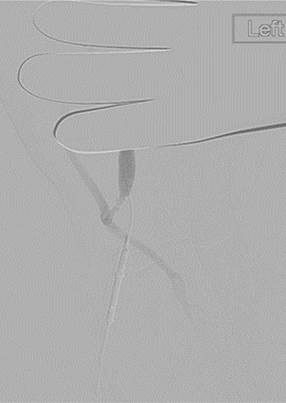

Fistulogram 4 months later (a).

Fistulogram 4 months later (b).